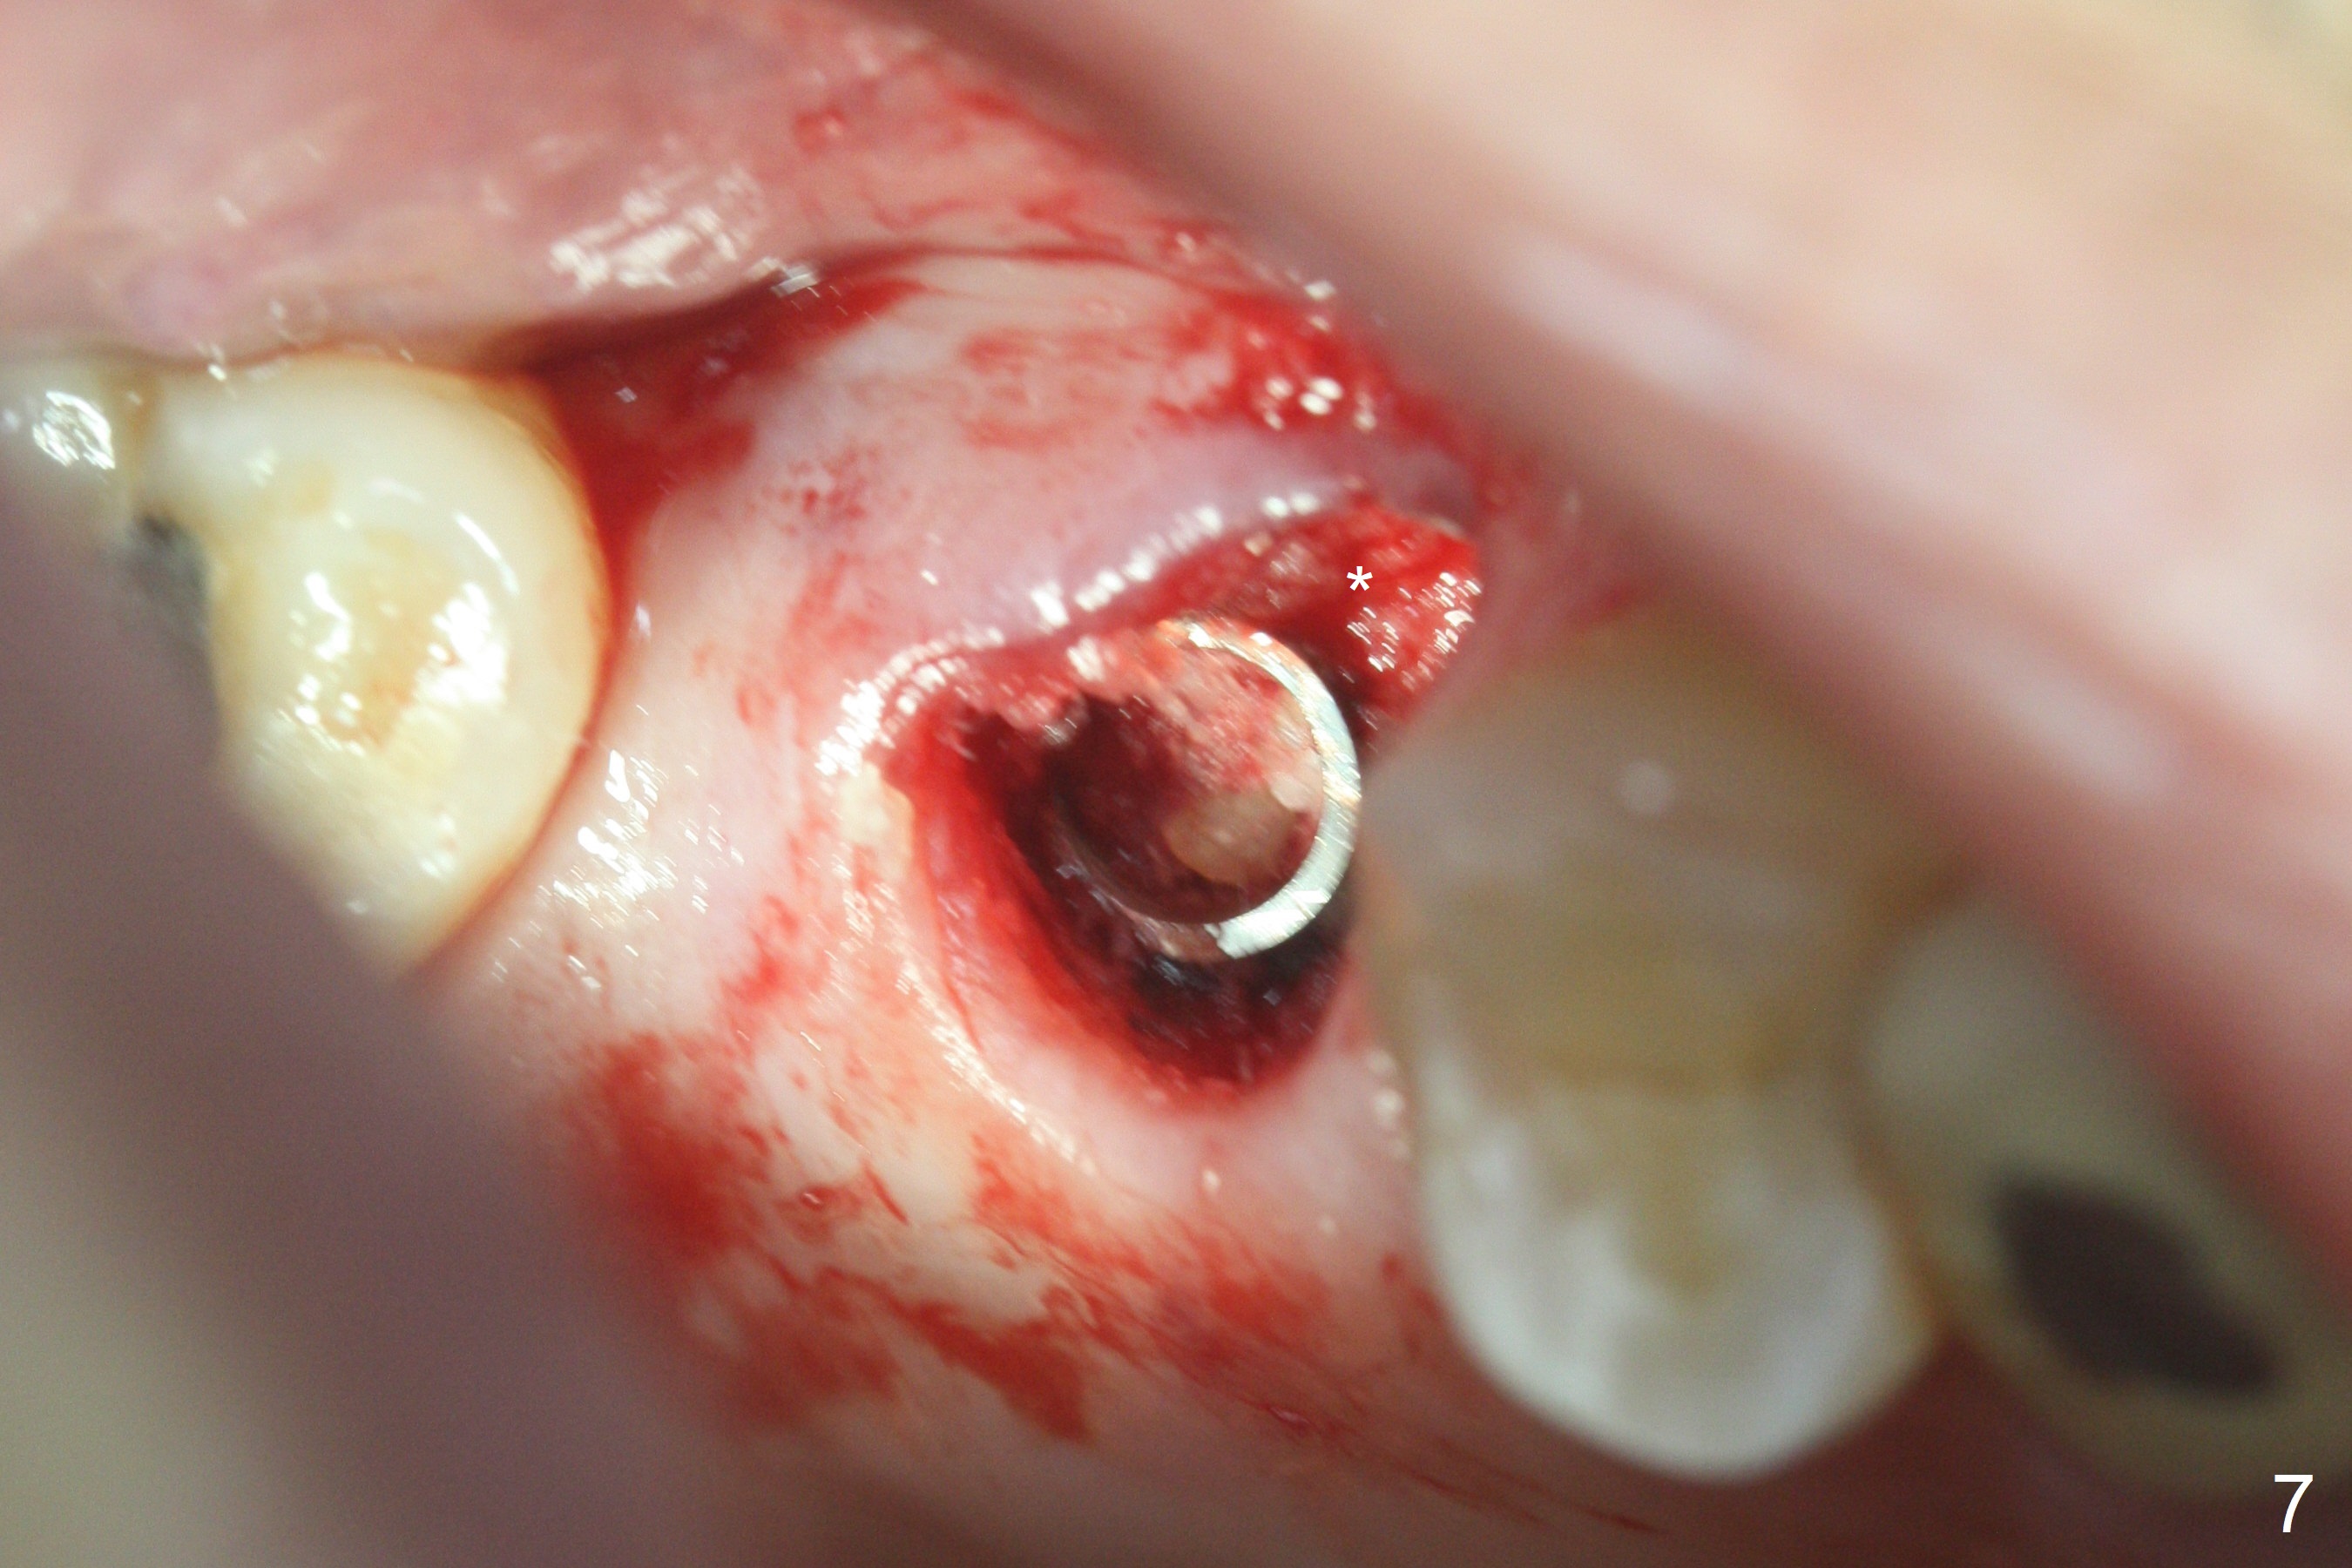

The palatal cusp of the affected 2nd premolar is apparently rotated distal (Fig.1). It is more obvious for the socket (Fig.2): the palatal (P) portion of the socket is more distal than the buccal (B) one. When the gauze is removed (Fig.3), Lindamann bur is used to remove the disto(D)palatal bone of the socket (data not shown), followed by starter drill in the DP wall obliquely (Fig.3'). Once the drill enters the bone for 1-2 mm, the bur is straightened and pushed slightly distal (Fig.3''). Fig.4 shows a parallel pin distal (overcorrect) to the original socket (Fig.4 red dashed line). Sequential osteotomy is conducted until 3.8x13 mm drill for 18 mm (Fig.5): note the 2 steps of the osteotomy (red lines). Since the apical portion of the osteotomy is larger than the drill, a larger implant than expected (5x16 mm) is placed. The implant ends up in the middle of the edentulous area (due to the stepped osteotomy; Fig.6-9; >60 Ncm). Vera allograft is placed (Fig.7-9 *) prior to and after placement of a 6.5x4(3) mm abutment (Fig.8-10). The remaining socket opening is sealed with a piece of Collagen plug (Fig.10 *). The socket is then closed by an immediate provisional (Fig.11 P). The abutment is retightened 2 months postop (Fig.12,13). The crown is cemented 4.5 months postop. Panoramic X-ray and CT are taken nearly 7 months post cementation (Fig.14,15) when the patient is ready for #30 implant guide preparation.